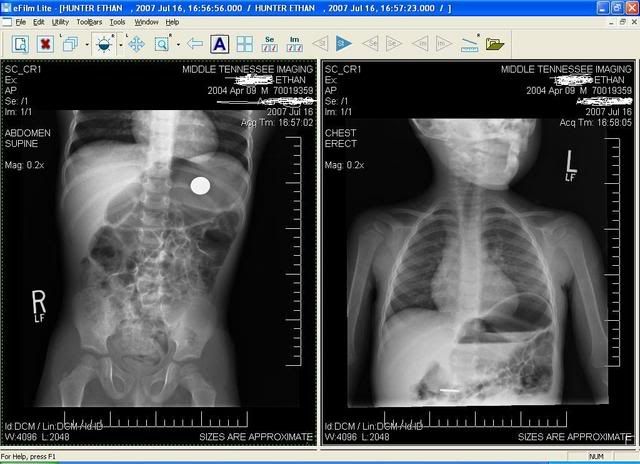

Oh thejoys of motherhood. my little boy (3 years old) swallowed a penny on Friday ... normally I don't freak out abotu this stuff but I foundthat pennies minted after 1982 are primarely zinc, with only a coating of copper. when zinc comes in contact with your stomach acid it becomes as corrosive as a car battery. if in there long enough it can cause ulcers and liver/kidney failure (well the liver and kidney failure would come with ingesting more than 1 penny but the ulcer could happen with just 1 penny). ANYWAY after 3 days of looking through poo there was no penny so we were informed to go to the Dr. and they did an x-ray tomake sure it wasn't stuck in his esophagus and hausing corrosion or burns to his esophagus. Luckely it has made its way to his intestines and is hopefully on its way out (which again YUCK I have to make sur eI find it otherwise after 7 days it is off tothe Dr for another x-ray andpossible surgical removal)

Here is an x-ray for your enjoyment lol it is pretty funny to look at and will I am sure make a great page in our scrapbook.